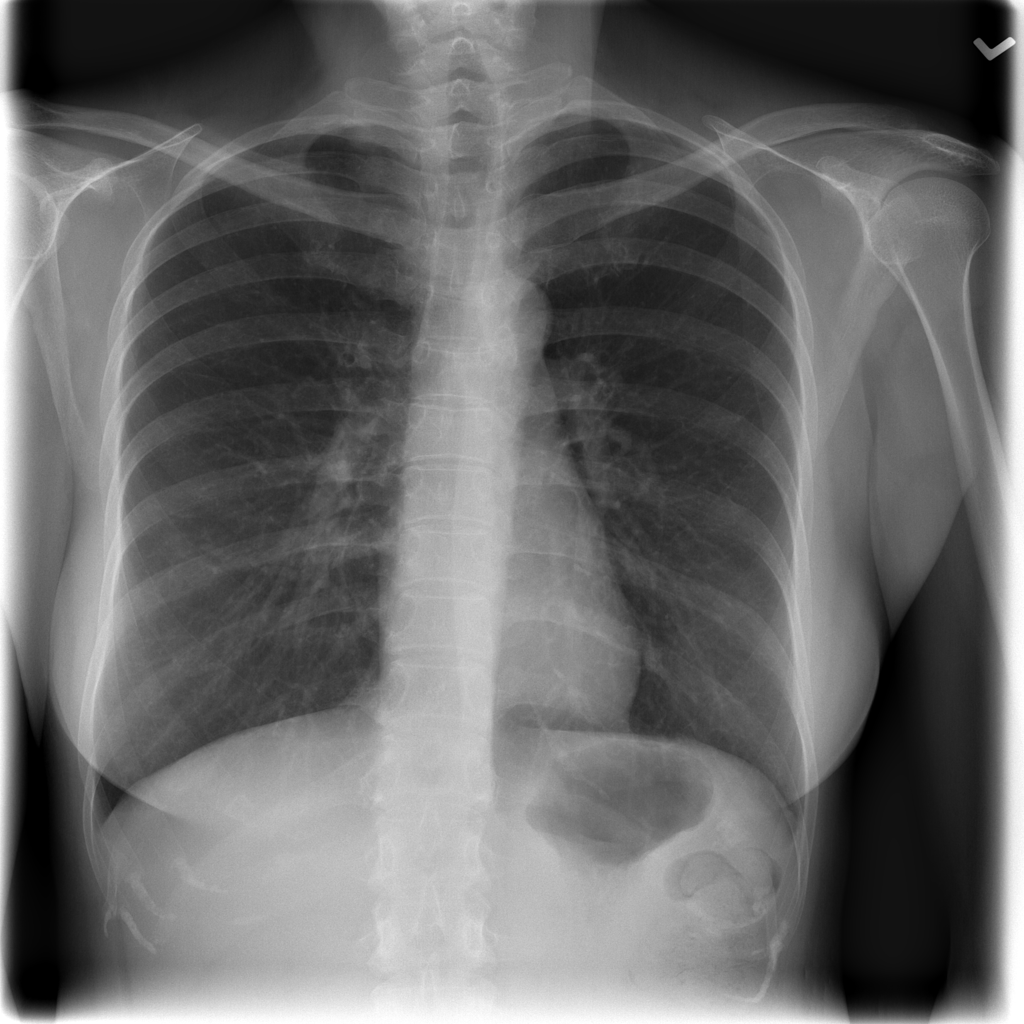

PAT-EBE1 · IMG-019Pneumonia

PAT-EBE1 · IMG-019

AP